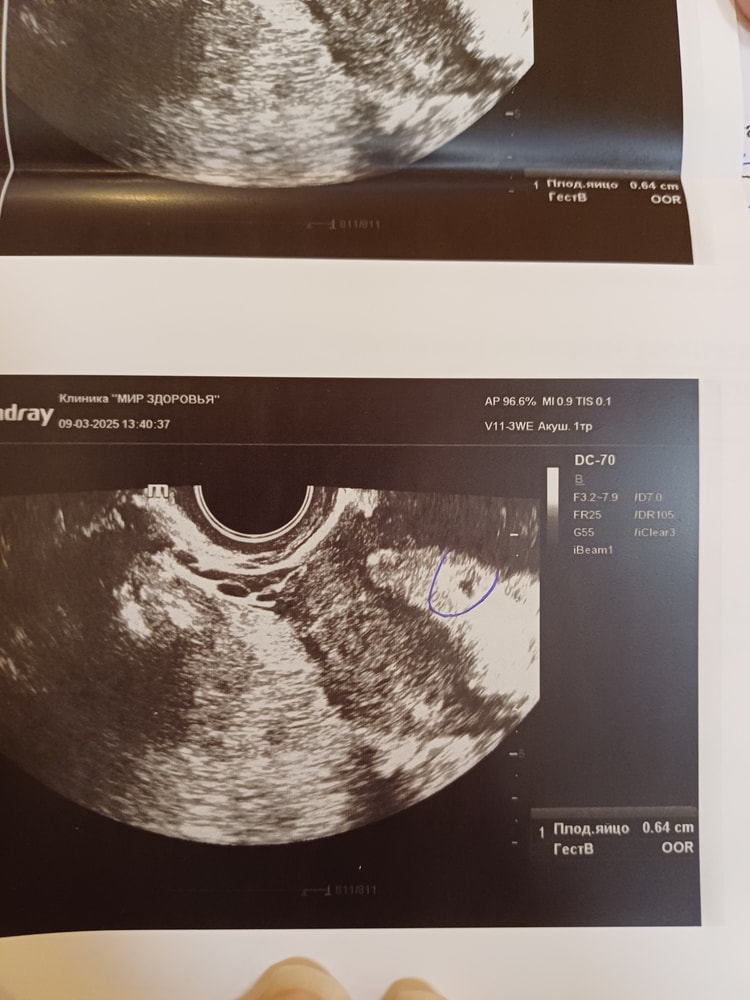

Вот покажу вам почему ждала я, у меня и при 4,8 мм и через неделю при 6,9 мм был желточный мешок. Поэтому мне говорили что есть маленькая надежда, но и то на втором УЗИ мне сказали что её уже нет, эмбрион уже должен быть. Если у вас на 6 мм ничего не было, то я думаю это было оправданное решение и не было необходимости что-то ждать.

вот у меня ручкой обвели пя. Сказали просто черный глазок.показали.внутри ничего не было, про жм ничего не говорили. Но эта врач сказала может поздняя овуляция. А уже другая сказала.что с таким размером пя в 6 нед (6.4 мм) ничего хорошего не ждать